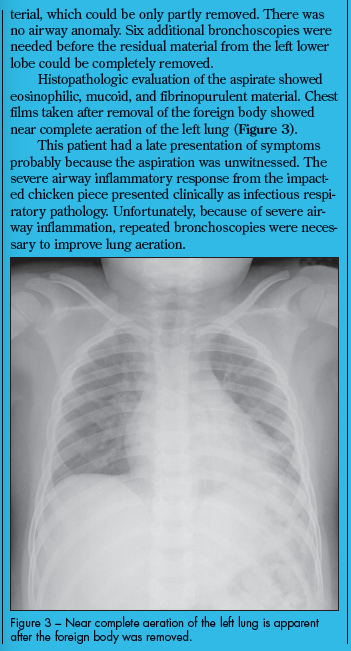

Divya Seth, MD; Milind Pansare, MD; Deepak M. Kamat, MD, PhD

Foreign-body aspiration is a relatively common occurrence in children.